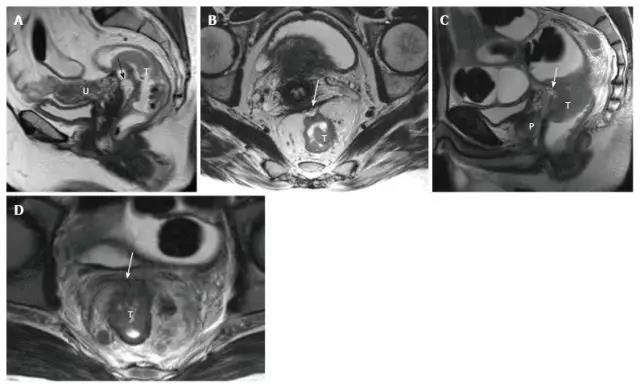

图 5. 女性(A 和 B)和男性(C 和 D)腹膜受侵 T4a 直肠肿瘤患者。在矢状位 T2 加权图像上,腹膜是肿瘤前面的低信号线性结构(A,C 中的箭头)。在轴位 T2 加权图像上,腹膜具有 V 形并且附着在直肠癌的前面(B 和 D 中的箭头)。T:肿瘤;U:子宫;P:前列腺。